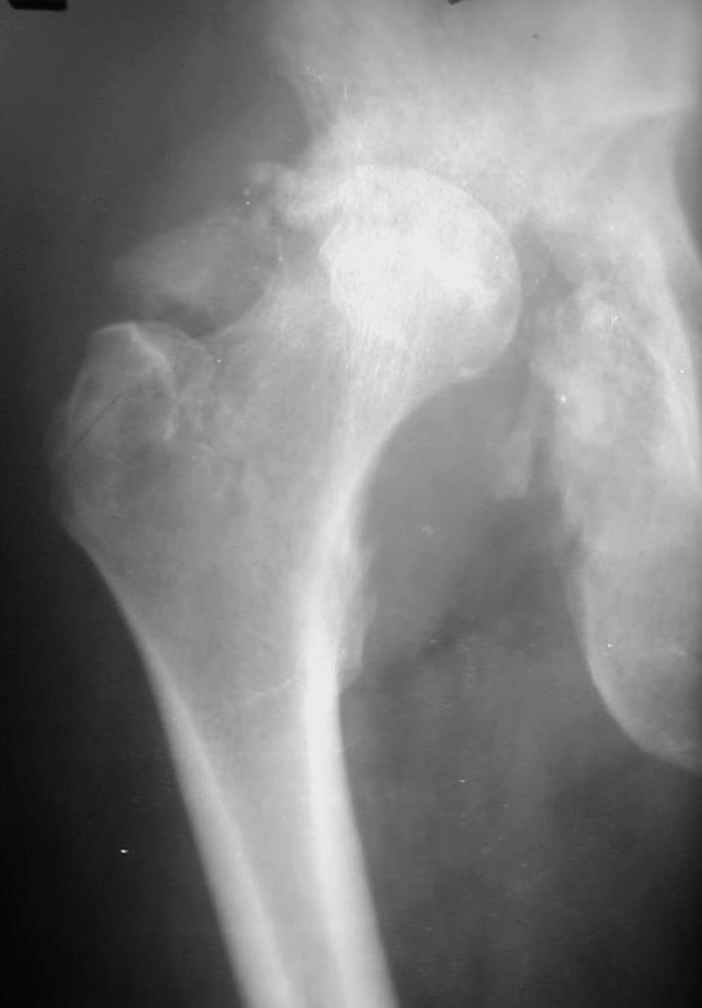

Уважаемые коллеги! На консультацию пришел молодой человек 23 лет с застарелым задним вывихомбедра. После травмы прошло 2,5 ГОДА.

Были переломы бедра и голени на этой же стороне, которые благополучно срослись после остеосинтеза. вывих бедра был пропущен. В настоящее время ходит без дополнительной опоры, есстественно, сильно хромает, выражен болевой синдром, парез седалищного нерва. Сформировался неоартроз в подвздошной области, виден неправильно сросшийся перелом задней колонны, сгибание в суставе до 80.

1.Большой костный посттравматический дефект вертлужной впадины. Поэтому необходима КТ для четкого планирования операции. При наличии контакта чашки с вертлужной впадиной на 55-60%% недопокрытие компенсируется за счет костной аутопластики собственной удаленной головкой (фиксация головки минимум 2-я винтами). Если недопокрытие большое, или не удается установить чашку, то можно установить кольцо Мюллера, опять же с костной пластикой.

В предлагаемой ситуации имеется последствия перелома задней колонны, что значительно больше усугубляет ситуацию, чем банальный дефект заднего края, и костного материала из головки может просто не хватить, тем более что в таком случае как раз вся нагрузка должна лечь на эту несчастную костную пластику. Наколько оправданы такие опасения, на Ваш взгляд?

Если у Вас есть дефект крыши, то никакая пластика не выдержит, лучше сразу ставить опорные кольца, все зависит от локализации костного дефекта.